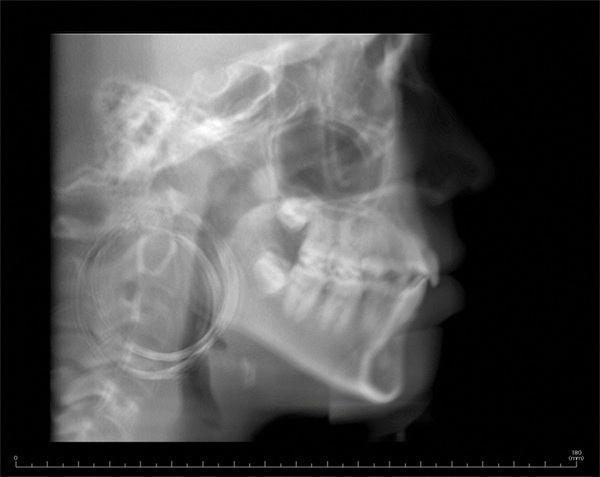

The final panoramic radiograph showed acceptable root positioning with no obvious radiographic evidence of significant adverse effects from treatment (Fig. 6). The final lateral cephalometric radiograph showed reduction in the protrusion of the incisors (Fig. 7). This reduction in incisor prominence was accompanied by a softer profile, more relaxed lips, and correction of the mentalis strain.

Fig. 7